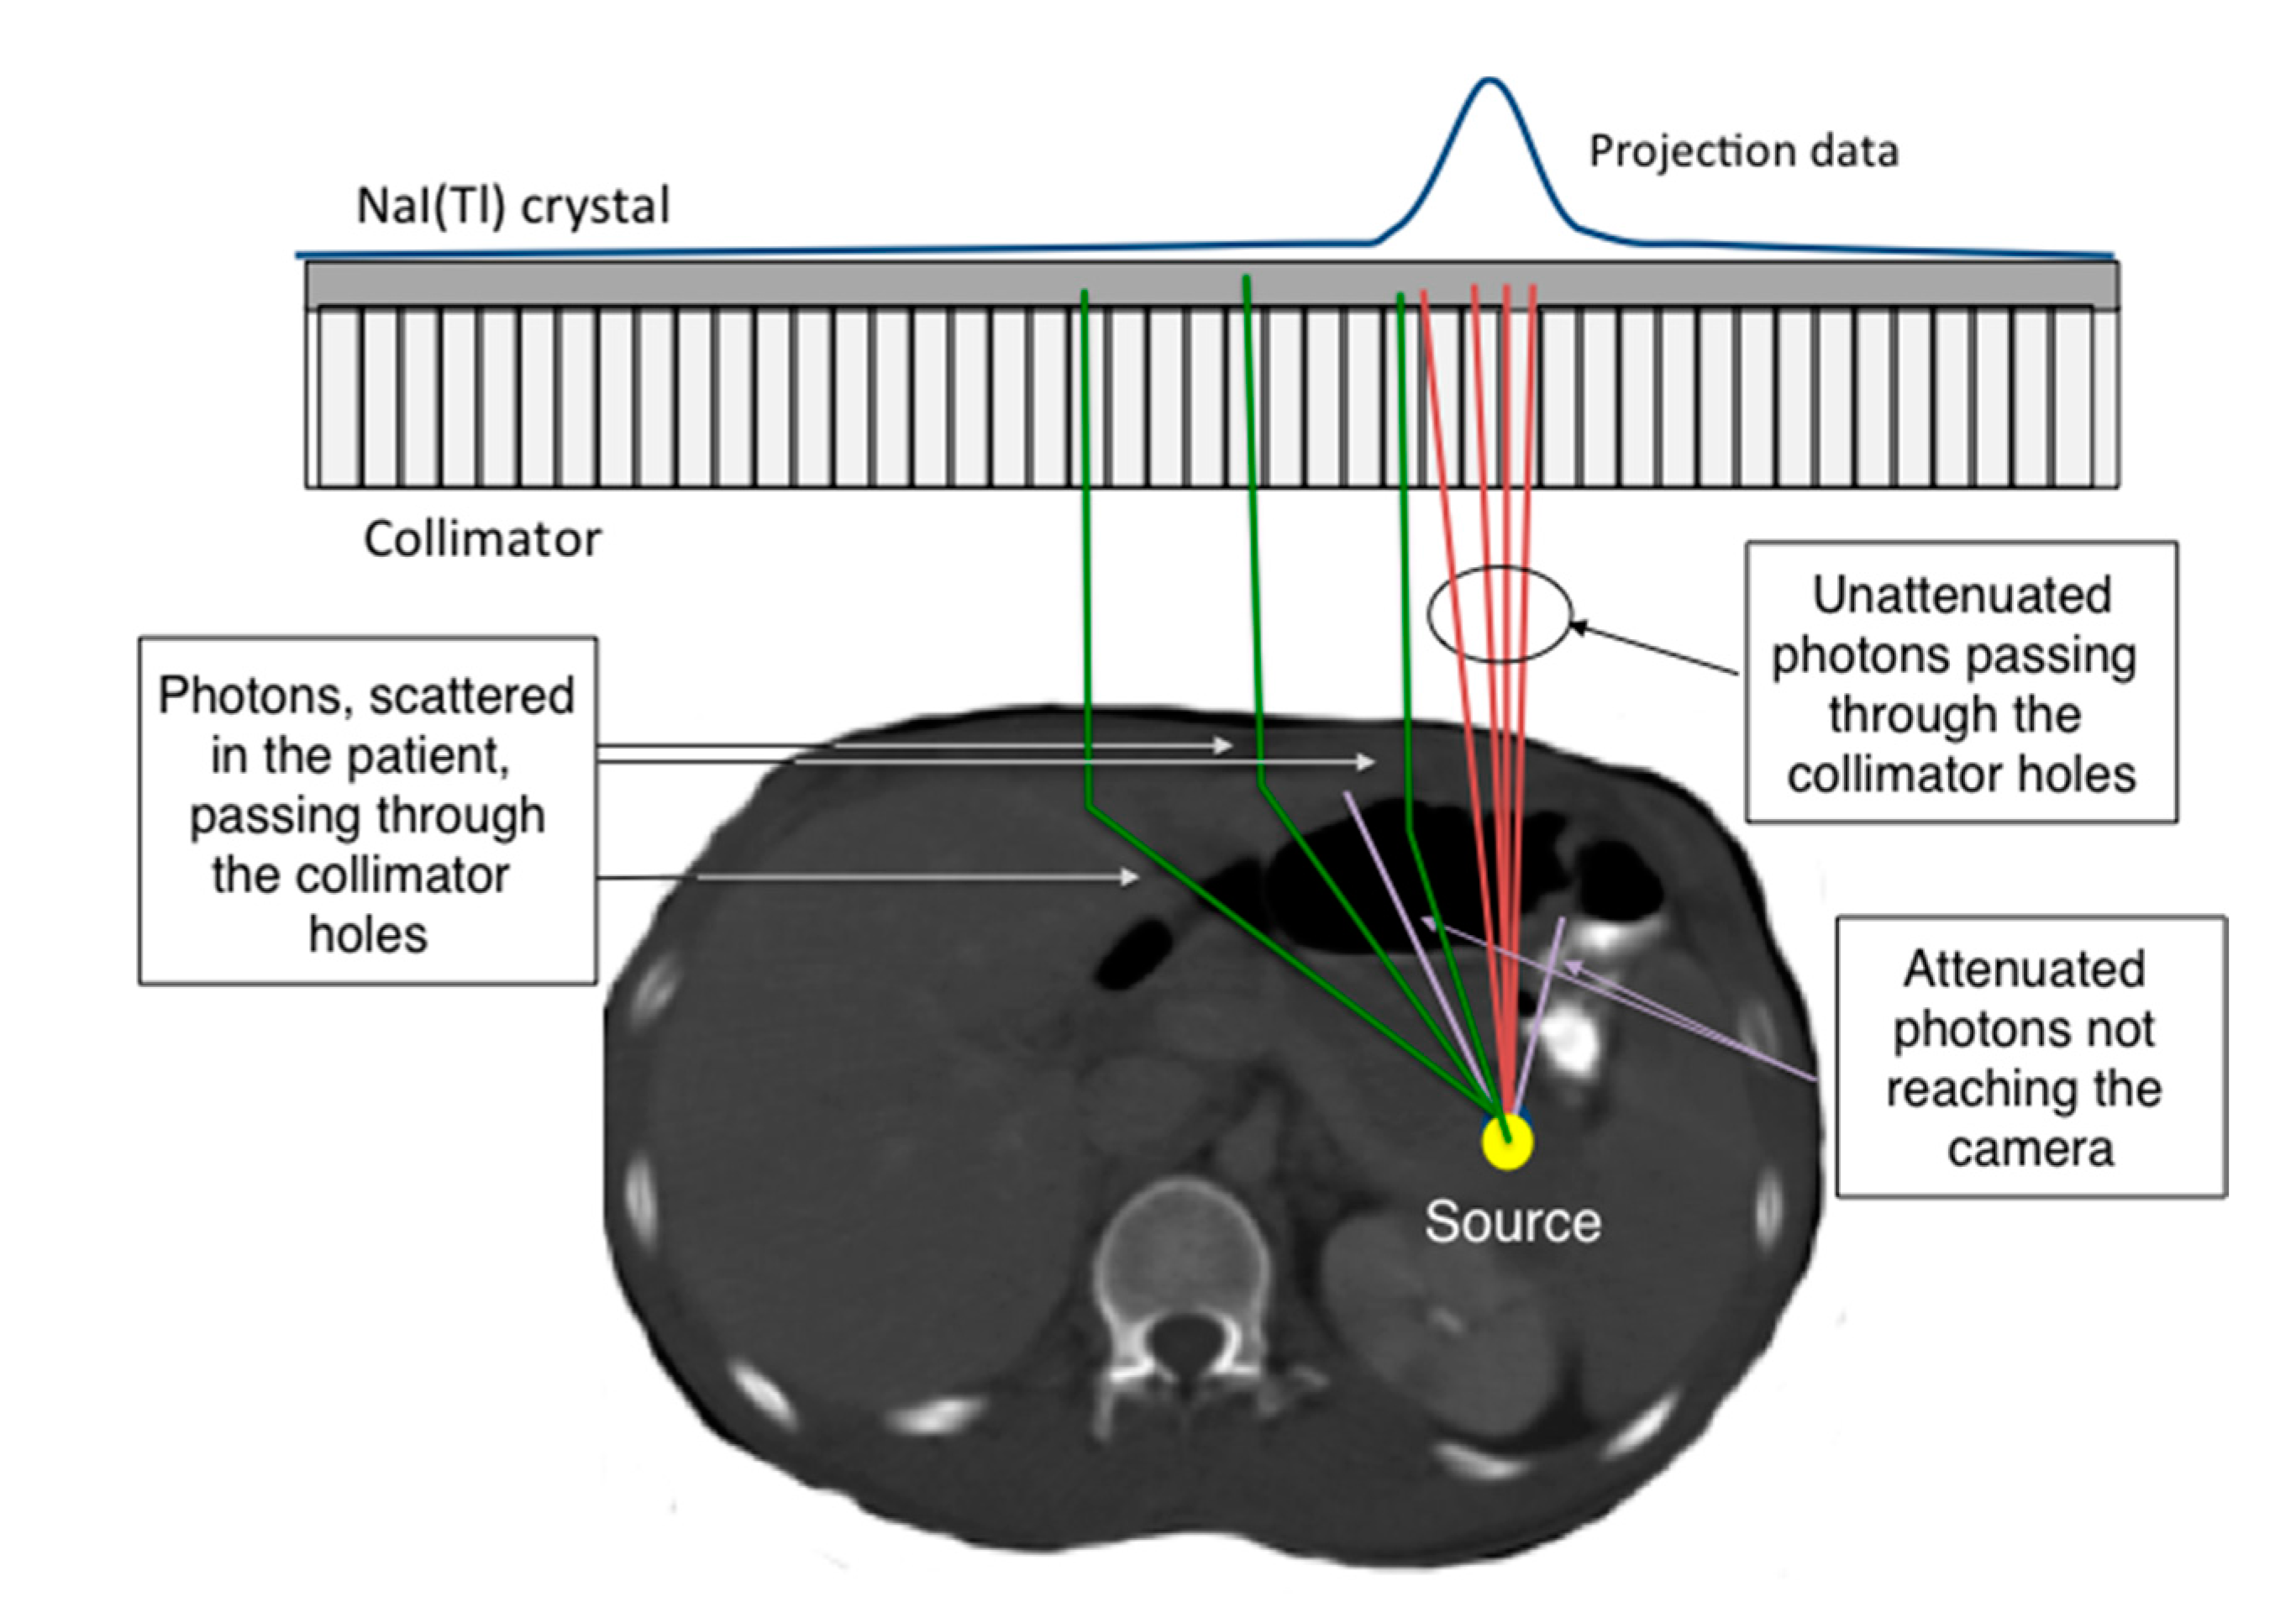

4.1. Photon Attenuation

4.2. Scatter Contribution

4.3. Collimator Resolution